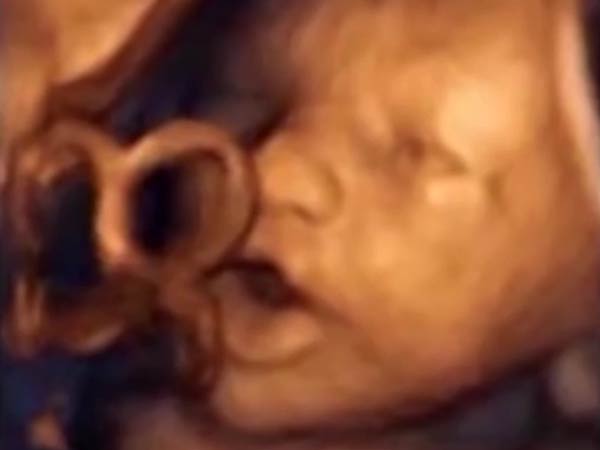

இந்த ஆய்வை தலைமையேற்று நடத்திய டாக்டர் மாரிசா லாப்சி இது தொடர்பாக கூறுகையில், ‘கர்ப்பத்தில் இருக்கும் 16 வார சிசு இசையைக் கேட்டு வாயை மற்றும் நாக்கை அசைப்பது கண்டுபிடிக்கப்பட்டுள்ளது. இது பார்ப்பதற்கு அக்குழந்தைப் பாட அல்லது பேச முயற்சிப்பது போல் தெரிகிறது.

இந்த ஆய்விற்காக பேபிபாட் என்ற இசைக்கருவி உருவாக்கப்பட்டது. இந்தக் கருவி மூலம் கருவில் இருக்கும் போதே குழந்தையின் மொழி திறனை வளர்த்துக் கொள்ளமுடியும் என்பது சிறப்பம்சமாகும்.

அதே சமயம் கர்ப்பப்பைக்கு அருகே சிறப்பு ஸ்பீக்கர்கள் மூலம் இசையைக் கேட்ட போது 87 சதவீதம் சிசுக்கள் தலையையும், மூட்டுப்பகுதியையும் அசைத்ததாகவும், ஒரே நேரத்தில் வாய் மற்றும் நாக்கை அசைத்ததும் கண்டுபிடிக்கப்பட்டுள்ளது.

ஆனால், இந்த அசைவுகள் எல்லாம் மியூசிக்கை நிறுத்தியதும் உடனடியாக நிறுத்தப்பட்டு விட்டதாக ஆய்வாளர்கள் கூறுகின்றனர். ஹெட் போன் மூலம் இசையை கர்ப்பிணிகளின் வயிற்றிற்கு அருகே வைத்த போது, சிசுக்களின் செயல்பாட்டில் எந்த மாறுதலும் ஏற்படவில்லை என்றும் அவர்கள் கூறுகின்றனர்.